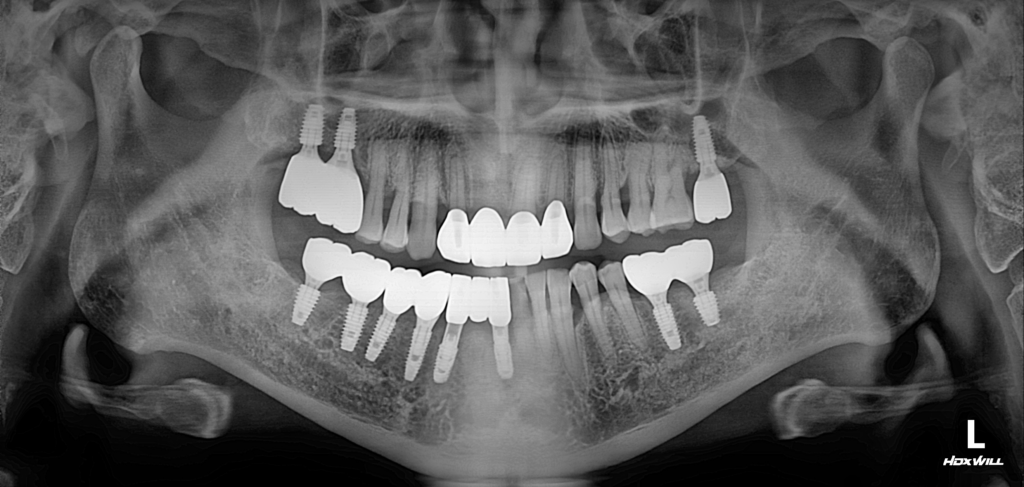

시술 후

26.10.07

26.01.07

치아 발치가 필요하다는 이야기를 들으면 많은 분들이 걱정을 하시지만, 최근에는 발치 후 임플란트 식립을 통해 치료 기간을 줄이고 자연스러운 결과를 얻을 수 있는 방법도 다양하게 시행되고 있습니다. 다만 모든 환자에게 즉시 식립이 가능한 것은 아니기 때문에 정밀 검사와 충분한 상담을 통해 개인에게 맞는 치료 계획을 세우는 과정이 중요합니다.